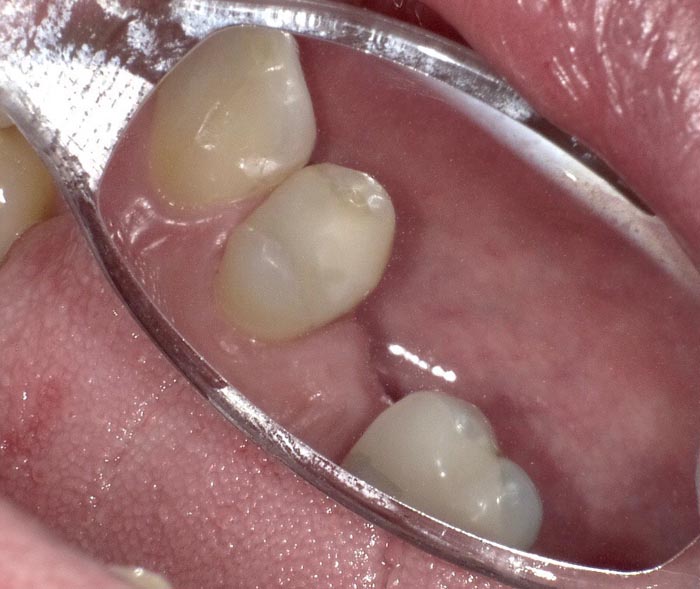

Case 3

A 62-year-old patient presented for restoration of #30.

• Figure 11

• Figure 12

• Figure 13

• Figure 14

• Figure 15